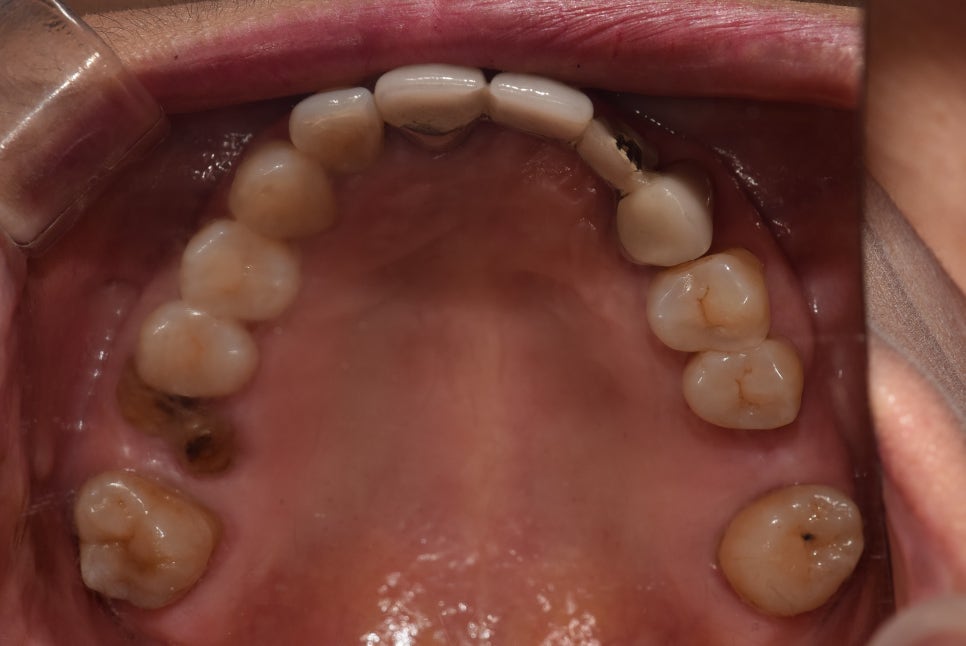

아하.. 양 옆 # 16, 26 어금니 소실을 겪었는데,

16번은 잔존치근이 있네요.

결국 거멓게 썩어버렸지만요..

판교 치과 는 이를 제거해버리고,

양 옆으로 임플란트를 심어드리는 계획을 수립했습니다.